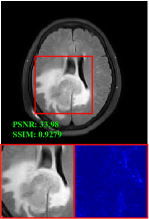

Figure 5 provides the qualitative comparison of the various methods on the four datasets at a scale of 4. The top, second, third, and bottom rows are the SR results under the FastMRI, clinical brain, clinical tumor and clinical pelvic datasets, respectively. The red boxes indicate the zoom-in region of complicated anatomical structures along with their corresponding error maps. Note that the brighter textures in the error maps, the lower the quality of the reconstructed images. As can be seen, compared to methods based on Transformers and CNNs, diffusion-based methods like DisC-Diff and DiffMSR (Ours) are capable of reconstructing high-realistic images with promising reconstruction metric scores (PSNR and SSIM). Nevertheless, while DisC-Diff can reconstruct high-precision MR images, it does not preserve the structure present in the original HR images, introducing some additional information that can affect medical diagnosis. In contrast, our method combines DM and PLWformer, which can preserve the original image’s structure while restoring high-frequency information.

In this section, we present more visual qualitative comparisons. Figures 8, 9, 10, and 11 show the reconstruction results of each method in FastMRI, clinical brain, clinical tumor, and clinical pelvic, respectively. As can be seen, although DisC-Diff can reconstruct MR images with high-frequency information, it fails to preserve the structure and content of the original Target HR image effectively, resulting in image distortion. In contrast, our proposed DiffMSR can restore high-frequency information while preserving the structure of the original HR image, indicating the effectiveness of the joint use of DM and PLWformer.